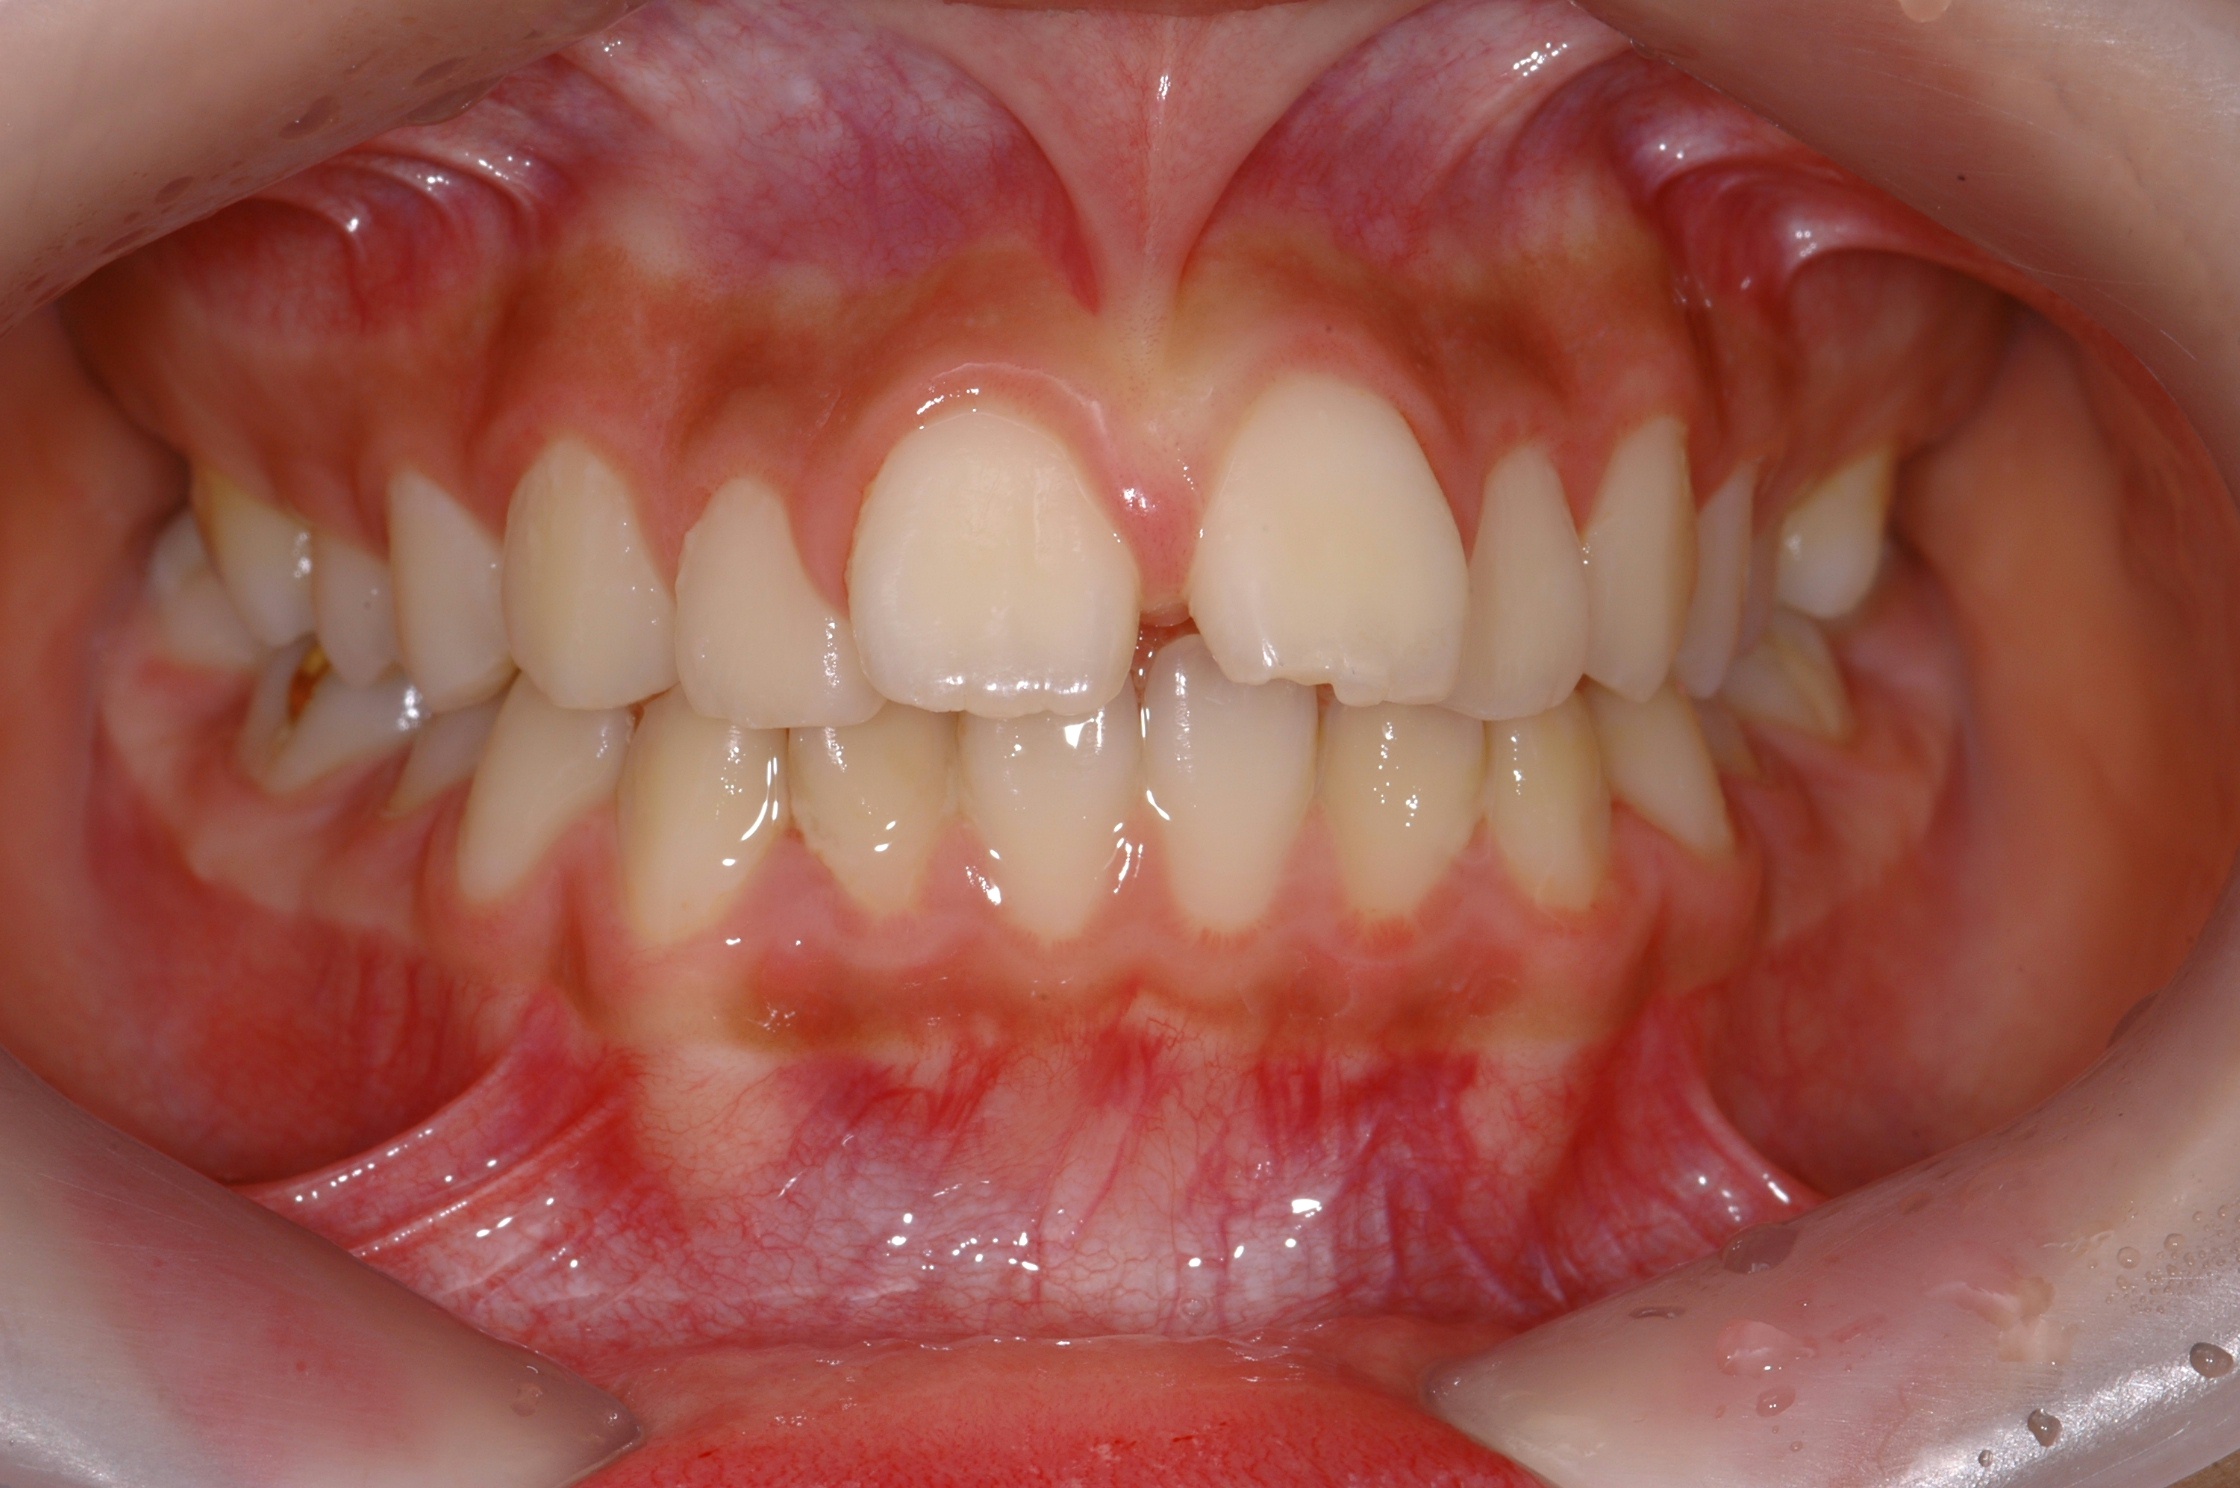

치료 전 사진입니다.